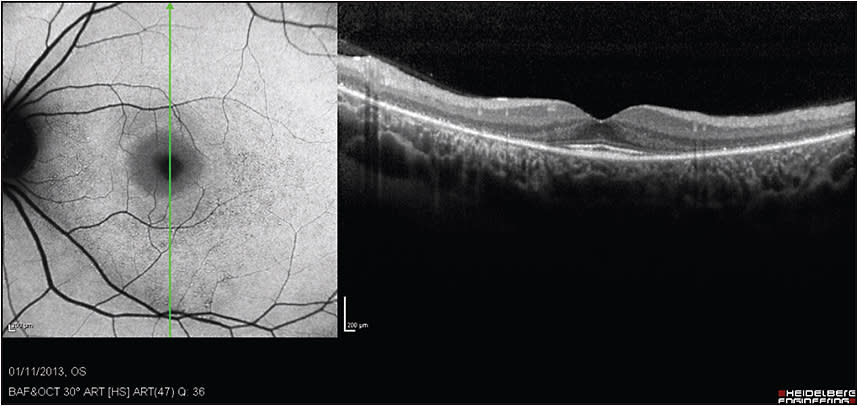

Figure 1. SD-OCT imaging of a 29-year-old woman treated with a daily dose of 400 mg of HCQ for 14 years. She complained of some disturbance in night vision. Her visual acuity was 20/20.

COURTESY OF HADAS NEWMAN, MD

Figure 2. SD-OCT imaging demonstrates perifoveal thinning of the ellipsoid layer and outer retina, with a preserved central fovea (the “flying saucer” configuration). FAF imaging demonstrates perifoveal hyperautofluorescence, surrounded by granular hyper-/hypoautofluorescence.

Typically, cases of HCQ toxicity may demonstrate parafoveal thinning and loss of the ellipsoid zone, with preservation of the foveal architecture — creating the “flying saucer” shape (Figures 1 and 2). Advanced cases may present with loss of the ellipsoid zone in the foveal area and also widespread diffuse thinning of the outer retinal layers.4

Fundus autofluorescence (FAF) can potentially identify abnormalities in the RPE. Due to its sensitivity, it is possible to see autofluorescence changes even in early HCQ toxicity. Early toxicity may present as fine annular hyperautofluorescence.2

With progression of retinopathy, atrophy of the photoreceptors and RPE develops and may present as granular hyper-/hypoautofluorescent rings (Figures 1 and 2), which gradually become hypoautofluorescent. Nevertheless, some patients present with atypical FAF findings, such as pericentral retinopathy, which has been described in Asian patients.5